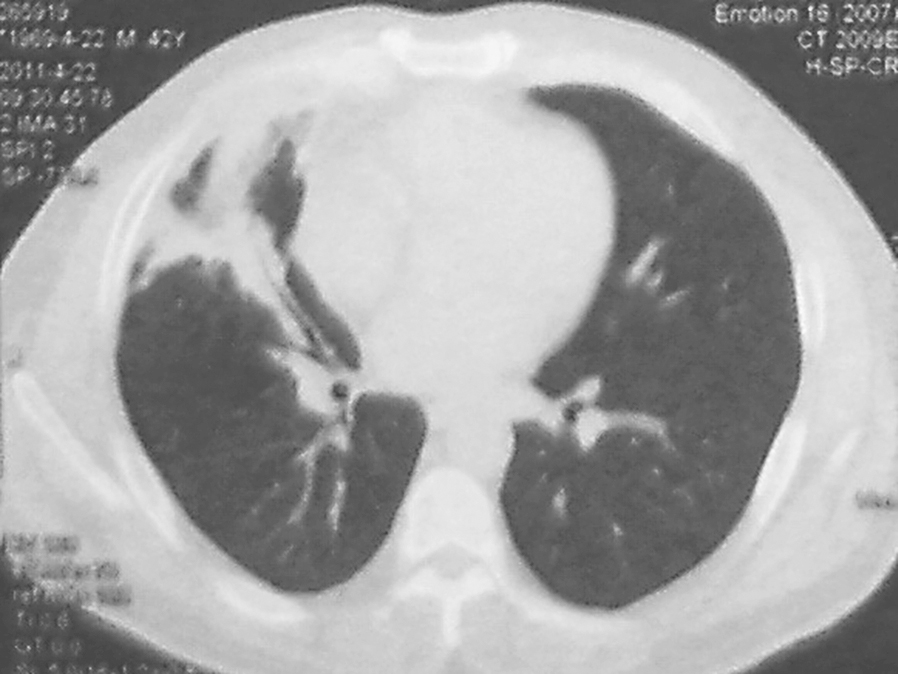

自2月18日起,患者体温高峰<37.3℃,采取抗感染降阶梯治疗,头孢哌酮联合舒巴坦(3g,每12小时1次)、克林霉素(0.6g,每12小时1次)、左氧氟沙星(0.5g,每天1次)5天,然后氨苄西林联合舒巴坦(3g,每8小时1次)、多西环素(0.1g,每天2次)7天。患者体温持续正常,咳嗽、咳痰明显减轻,于3月11日出院。出院后,口服抗生素多西环素(0.1g,每天2次)、阿莫西林克拉维酸(0.625g,每天2次)4个月。期间,患者于3月22日在当地医院行支气管镜检查,未见异常;4月22日复查胸部CT示右肺空洞消失,遗留粗大索条、局限性胸膜病变(图4);7月28日复查胸部CT示右中叶索条影(图5)。

图4 复查胸部CT表现(2011-04-22)

图5 复查胸部CT表现(2011-07-28)